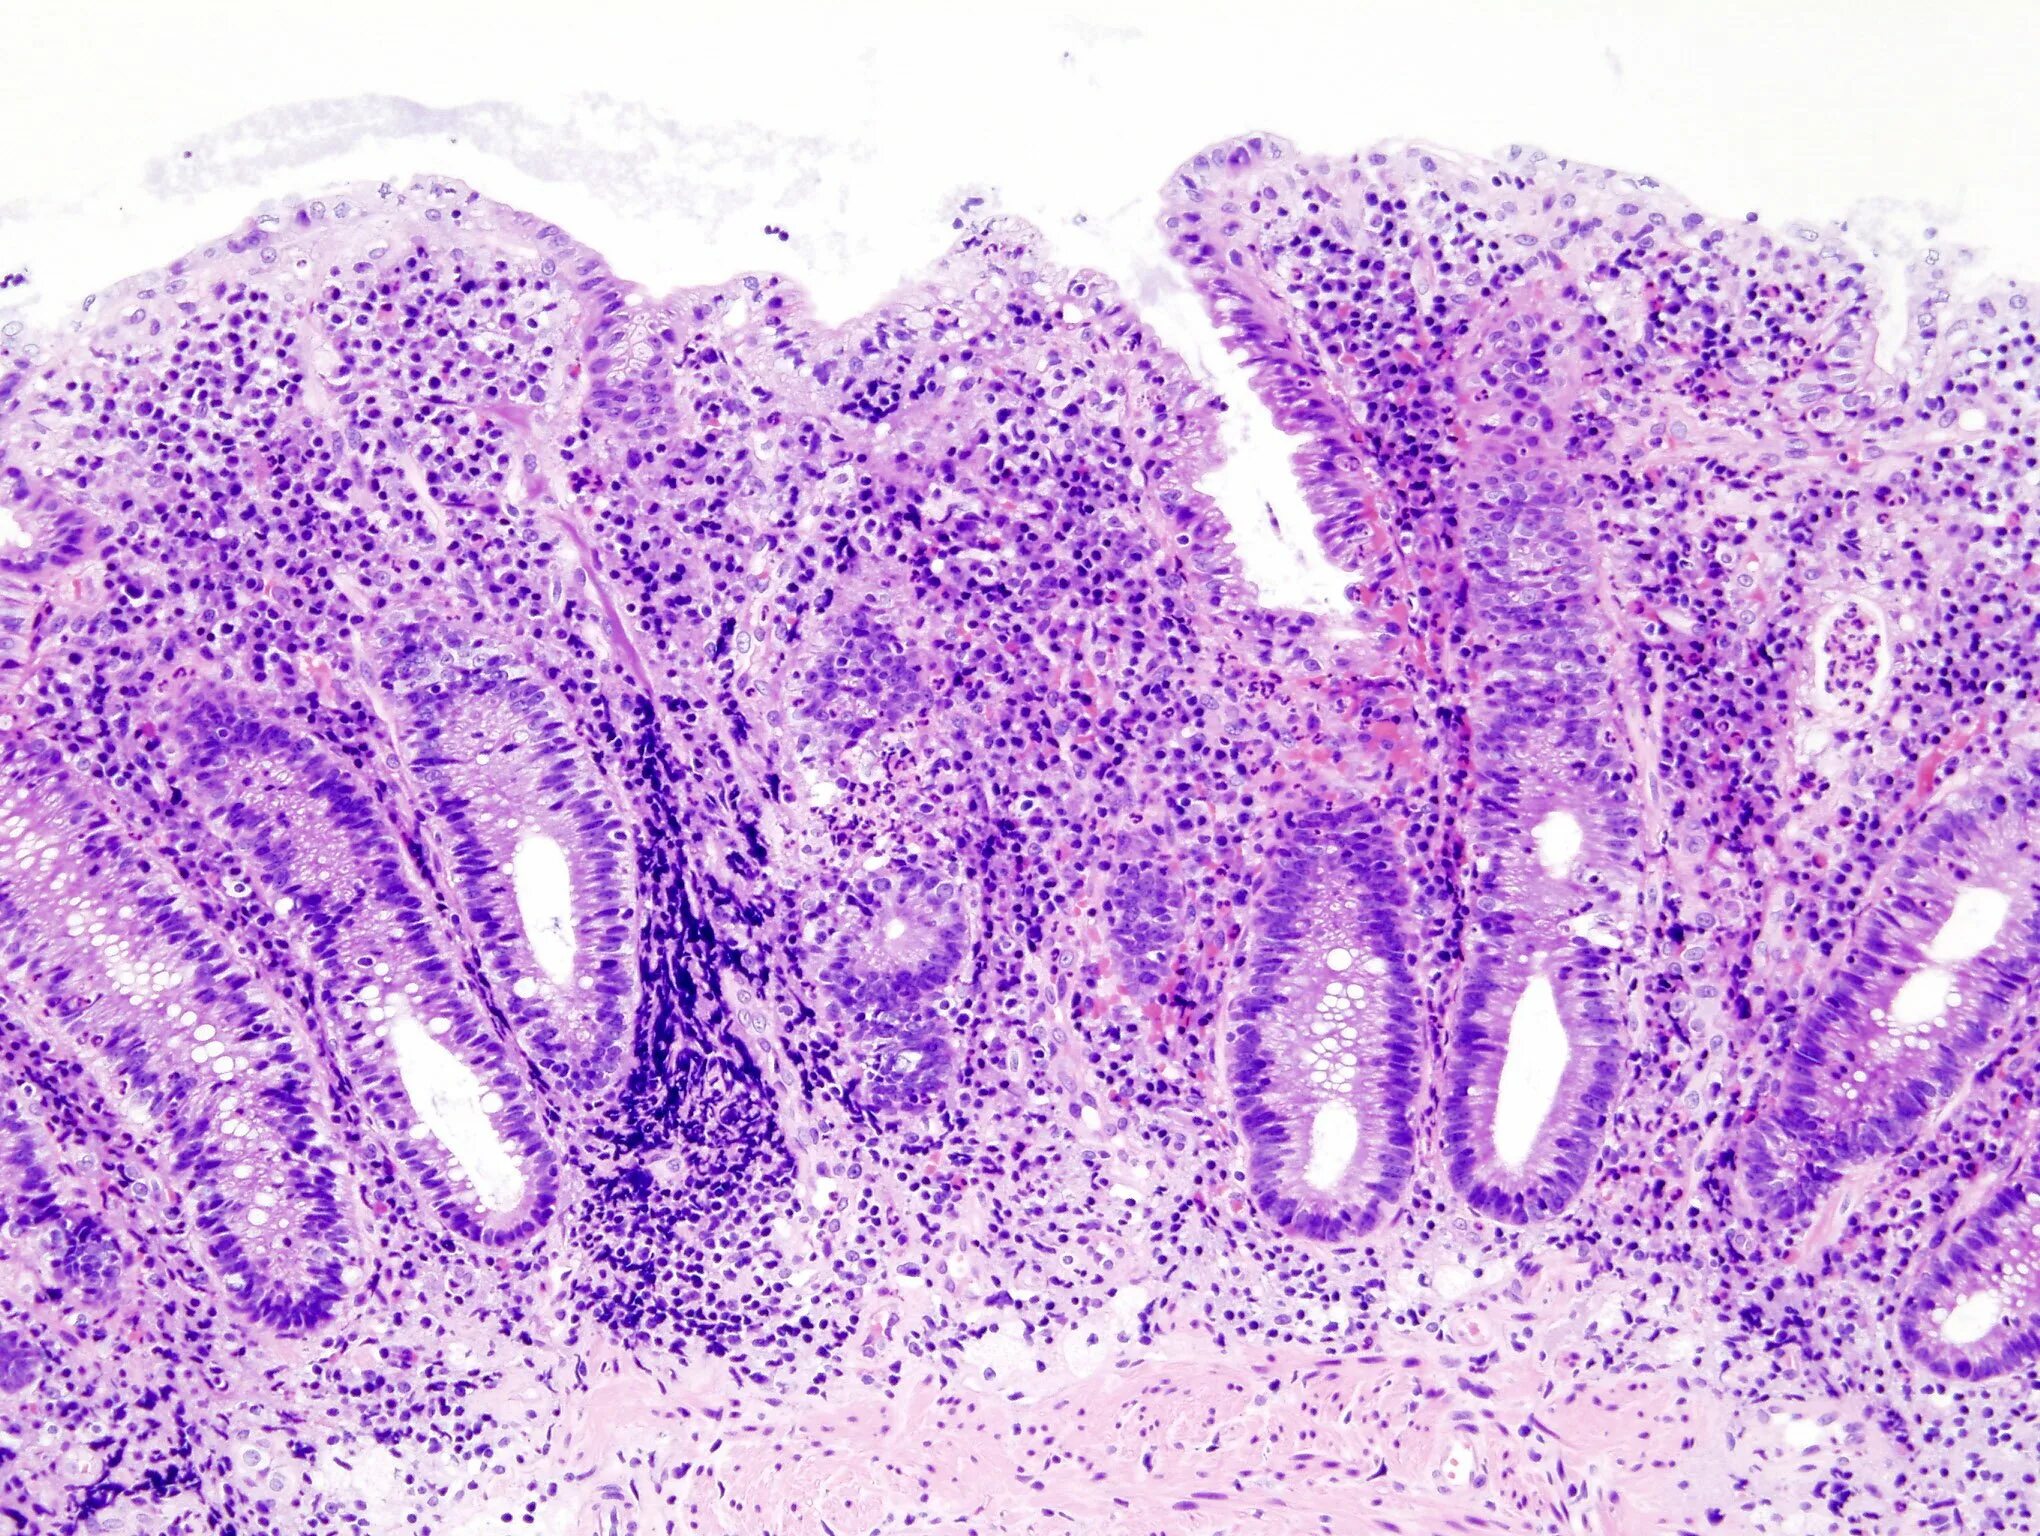

Гистологическое исследование слизистой